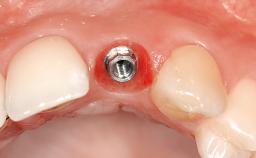

Surgical SAC classification

| Placement Protocol | - |

| Tooth Site | - |

| Socket Morphology | - |

| Socket Integrity | - |

Prosthodontic SAC Modifiers

| Soft Tissue Contour and Volume | - |